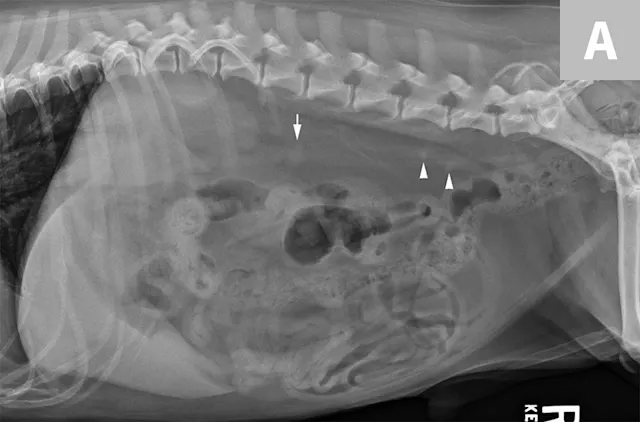

FIGURE 1A

Ventrodorsal radiograph of a normal cat for evaluation of the kidneys (arrows). Note the bean-shaped appearance, smooth capsular margin, normal size (approximately 2.2× the length of L2) and location. Both kidneys are more readily seen in this cat due to the amount of retroperitoneal fat. In the dog, the left kidney is easier to identify and evaluate routinely than the right, as the cranial pole of the right kidney border effaces with the renal fossa of the caudate lobe of the liver.